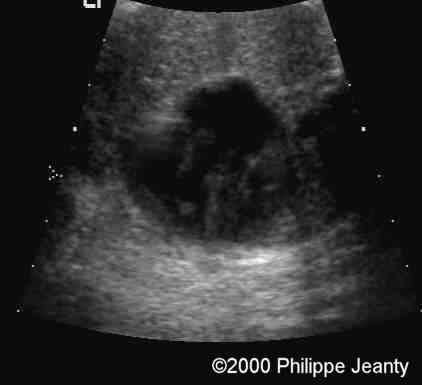

Humerus and femur (below) are too small (see chart below).

Femur

case0020-3

The femur (and humerus are way below the 5th percentile).